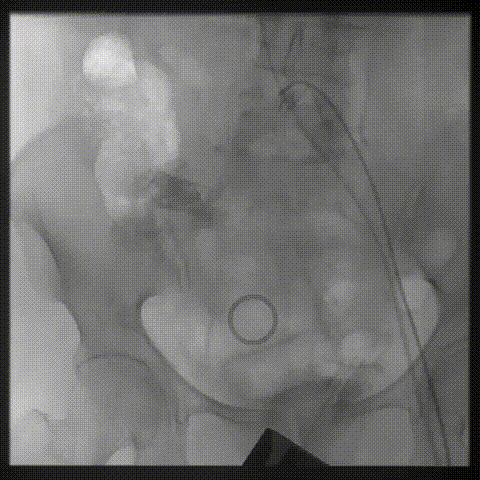

双侧侧髂血管造影血管纤细

LCA保护下18mm球囊预扩,扩张充分,瓣叶向LCA开口偏移;输送器过弓顺利。